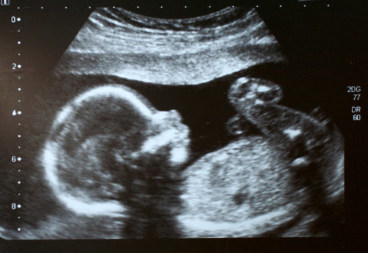

Londoner Forscher haben das Projekt iFIND gegründet und eine neue MRT-Technik für schwangere Frauen entwickelt. <br /><br />Diese bildgebende Technik ist sowohl für Mutter als auch für Fötus sicher. <br />Die Mutter liegt mit der Ausrüstung auf dem Bauch in einer Maschine, einem engen Tunnels gleich. <br />Die Untersuchung dauert ca. 30 Minuten. <br /><br />Die Magnetwellen des MRT empfangen dann Bilder in hoher Auflösung. <br />Diese fetale MRT-Technik ist ab der 20. Schwangerschaftswoche möglich. <br /><br />Eltern und Ärzte erhalten so relativ klare Videos von dem Baby. <br />Im Gegensatz zur Ultraschalluntersuchung können mögliche Komplikationen sehr früh erkannt werden, so dass eine entsprechende Behandlung so schnell wie möglich stattfinden kann.